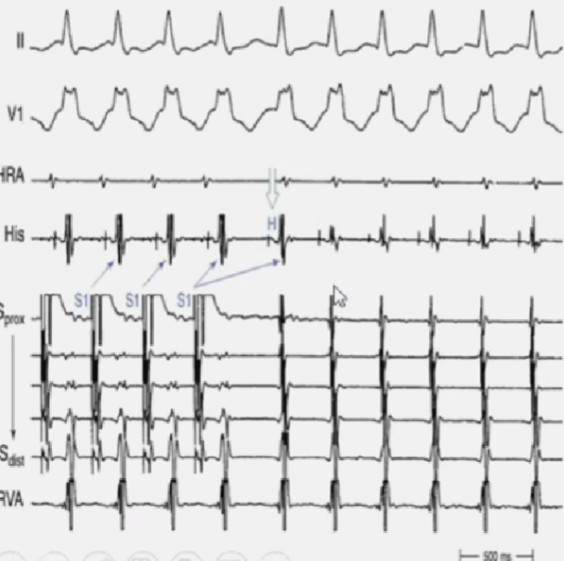

心室超速起搏(“拖带”刺激)VOP

-

比心动过速周长短10-30ms的周长发放刺激。

心房频率等同于刺激频率。

停止刺激时,心动过速持续。

心室超速起搏VOP(VAAV)

解释VAAV:

AT时,刺激心室出现1:1室房逆传,逆传经经房室结传导,由于房室结前向传导处于不应期,心室刺激最后一个逆向心房波不能经房室结下传心室,心室刺激终止(VA)后,接着是房速继续的心房波(A)和下传的心室波(V),即VAAV

心室超速起搏VOP(AVA)

解释VAV:

AVRT和AVNRT时,心室快速刺激拖带心室,室房经折返环的逆传支传导,在最后一个心室刺激后,经逆传支激动的心房波,由于折返环的前向支已经脱离不应期,可以通过前传支下传心室,产生最后一次心室刺激(V)后,逆传心房(A),经前传支下传激动心室(V),即VAV,心动过速继续。